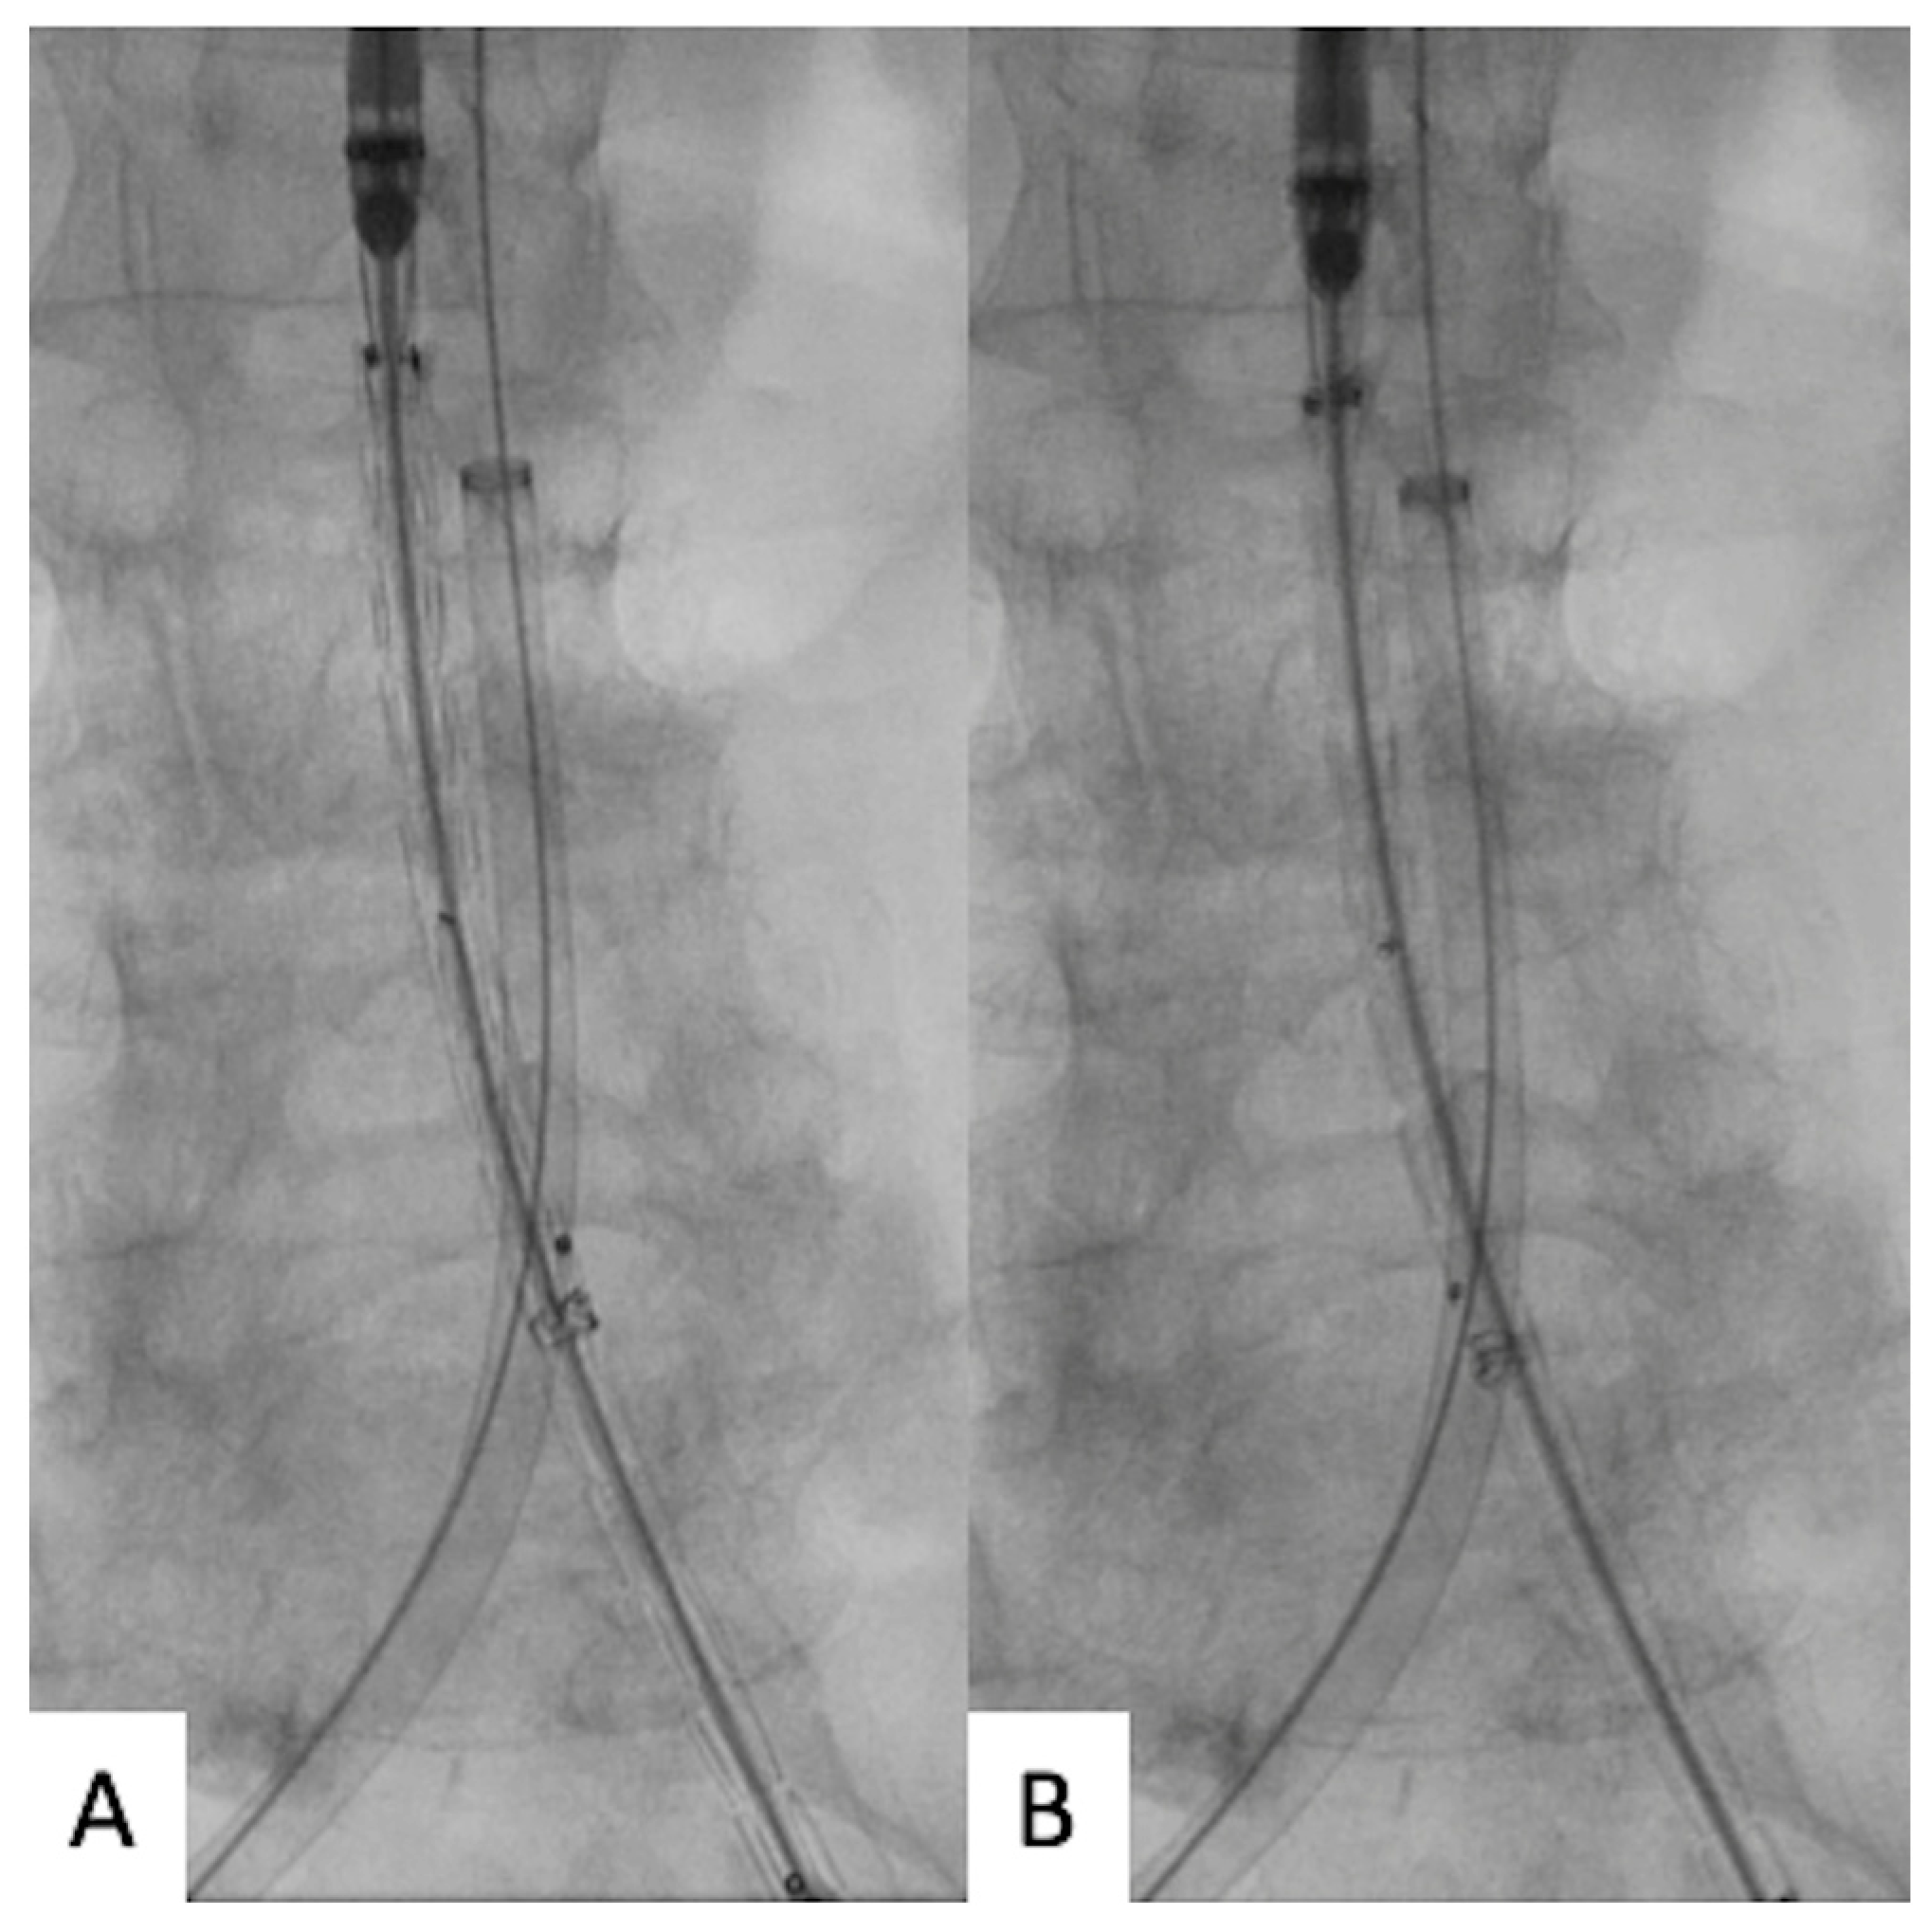

The contralateral 10 Fr sheath on the intended main body introduction side was exchanged for a 30 cm 12–18 Fr Dryseal introducer sheath (W. L. Gore & Associates, Medical Products Division, Flagstaff, AZ, USA) over the stiff wire and advanced into the aorta at the level of the lowest renal artery. A short dilator was employed to place it parallel to the stiff wire; an additional 0.035-inch standard J-tip guidewire was applied through the Dryseal introducer. A 5 Fr pigtail angiographic catheter was advanced over the standard J-tip guidewire into the aorta above the level of the renal arteries (Figure 1).

Figure 1.

(A) Short dilator and parallel 0.035-inch standard J-tip guide-wire through the Dryseal introducer. (B) A 5 Fr pigtail angiographic catheter advancement.